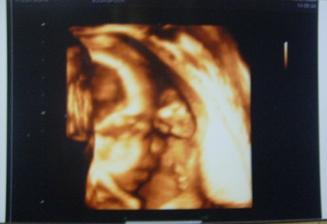

Náš Matýsek 20.11.2009

Narodil se 20.11.2009(na Nikolčin svátek:o))),váha 4150g,délka 55cm-uffff:o)))Je to naše zlatíčko:o)))